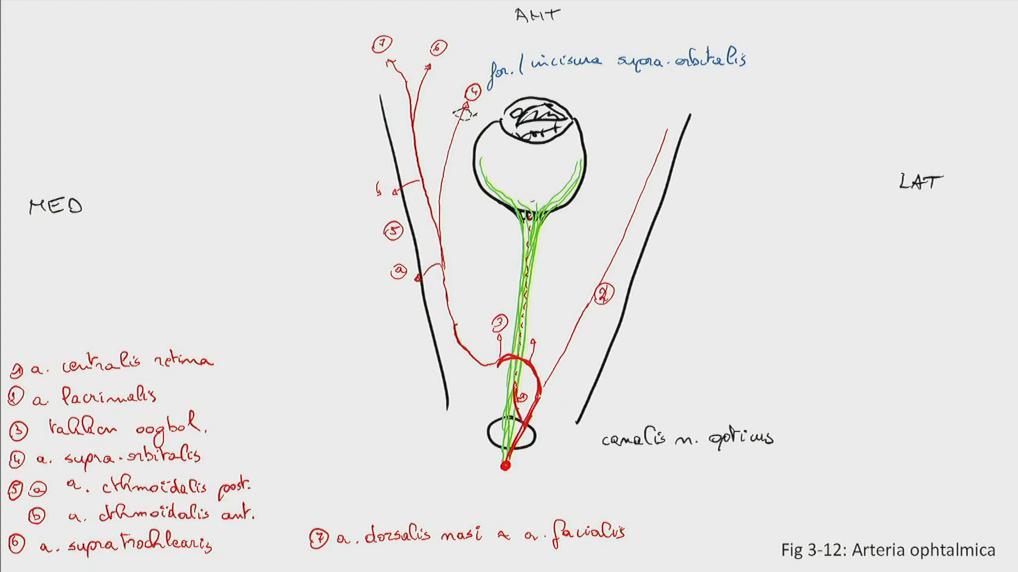

Fig 3.12: a. ophthalmica

orbita canalis n. opticus n opticus + retina (groen) a centralis retina (in n. opticus) a lacrimalis takken oogbol a supraorbitalis (via foramen/incisura supraorbitalis naar huid) a ethmoidalis posterior (via foramen ethmoidale posterius naar neus) a ethmoidalis anterior (via foramen ethmoidale anterius naar neus) -

eindtakken

|